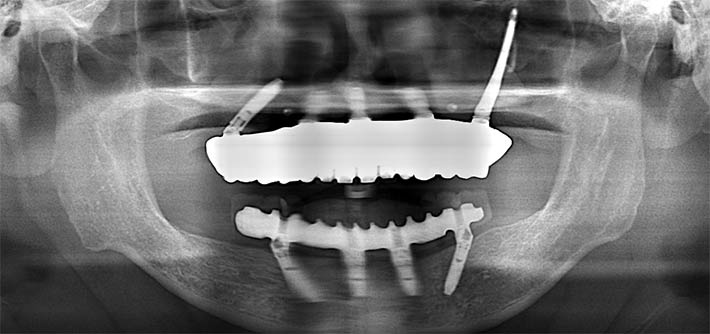

パノラマX線

上顎CT

術前の計画通りにインプラントが埋入されている事が確認できる